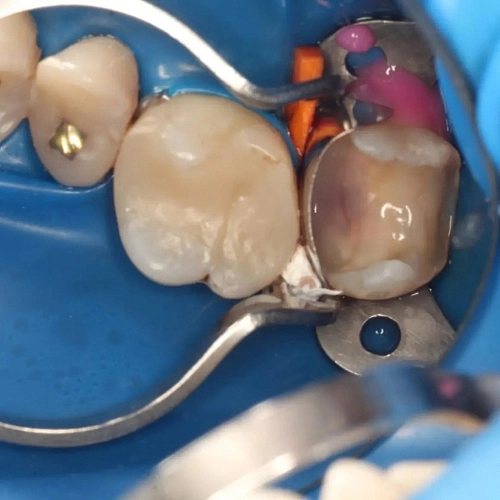

На фотографии представлена работа врача стоматолога Морозовой Александры Сергеевны, где зуб успешно подготовлен к дальнейшему протезированию.